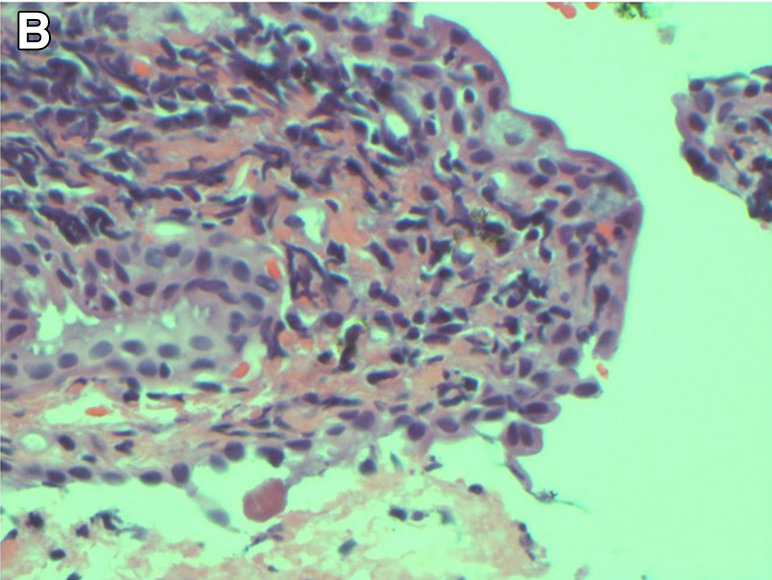

Η Τερέζα και η Δρ Ντάνα Ρόμπεϊ έδωσαν στη δημοσιότητα τις φρικτές εικόνες για να δείξουν τους κινδύνους του να μην αφαιρείται τη μάσκαρα το βράδυ πριν πέσετε για ύπνο.

Η Δρ. Ρόμπεϊ, που δημοσίευσε μια μελέτη για την περίπτωση της Τερέζα, είπε πως δεν είχε ξαναδεί και παρόμοιο και πως κινδύνευε να μείνει τυφλή και πρόσθεσε πως ελπίζει ότι η περίπτωση αυτή θα είναι μια σημαντική πλατφόρμα για την ευαισθητοποίηση σχετικά με τους κρυφούς κινδύνους των καθημερινών προϊόντων ομορφιάς.